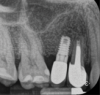

Among the factors associated with the appearance of this pathology are: contamination of the implant surface or surgical bed,11,12 overheating of bone during implant bed preparation,11,13 preparation of an implant bed that is longer than the implant itself,8 pre-existing bone disease,1 presence of residual root fragments or foreign bodies,8,11 premature loading causing bony microfractures,14 and implant placement in proximity to an infected maxillary sinus.14 Some studies have suggested the most likely cause is endodontic pathology of the tooth replaced by the implant or adjacent tooth.9,10 Figure 2 shows an intraosseous tract within the mandible from a periapical lesion of a tooth leading to RPI of the adjacent implant.

Fig 2. Panoramic radiograph (left) and CBCT (right) showing intraosseous tract from a periapical lesion of a tooth leading to RPI of the adjacent implant.

Figure 2